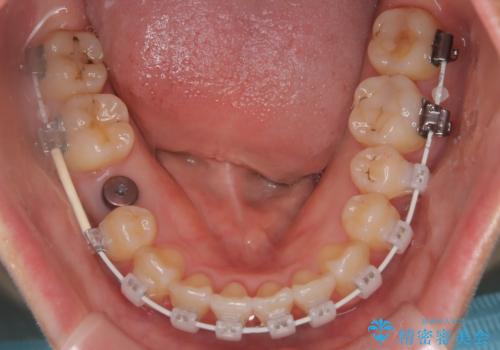

- 矯正装置

- 審美装置

- 患者様は、右下第2小臼歯(5番)の先天欠如により乳歯が残存している状態でした。

加えて、**下顎前歯部に叢生(歯のがたつき)**が見られ、審美的・機能的な改善を希望されて来院されました。

また、欠損部にインプラントを埋入するには、前後の歯の傾斜改善とスペース確保のための矯正治療が必要でした。

下顎前歯の叢生も同時に改善できるよう、全体的なワイヤー矯正による治療計画を立案しました。